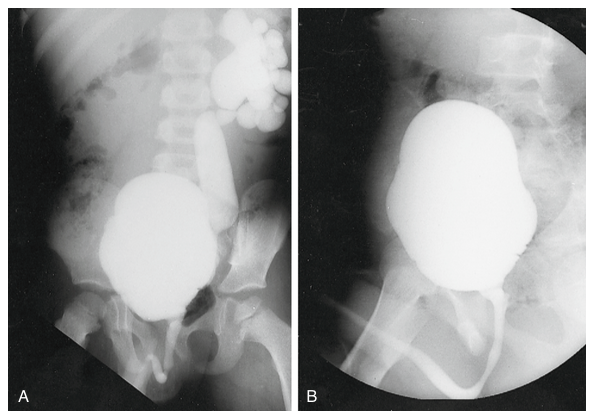

| A) CUMS mostrando RVU de alto grado Izquierdo. B) CUMS un año despues de tratamiento con Inyección endoscópica |

• Ecografía de las vías urinarias y CUMS para diagnosticar el grado del reflujo y establecer las causas reversibles (Fig. 15.2)

CISTOURETROGRAFÍA MICCIONAL SERIADA (CUMS)

Consiste en la instilación de contraste retrogrado, y control fluoroscópico permitiendo la observación dinámica durante la fase de llenado y la fase de vaciado vesical. Es el estudio más importante para la valoración del tracto urinario inferior en niños. La CUMS puede cuantificar el grado del reflujo y predecir el pronóstico del RVU. El sistema de clasificación más aceptado en esta patología es el Estudio de Reflujo Internacional (IRS) el cual contempla 5 grados de reflujo. Adicionalmente el CUMS permite la valoración de la uretra y de la vejiga.